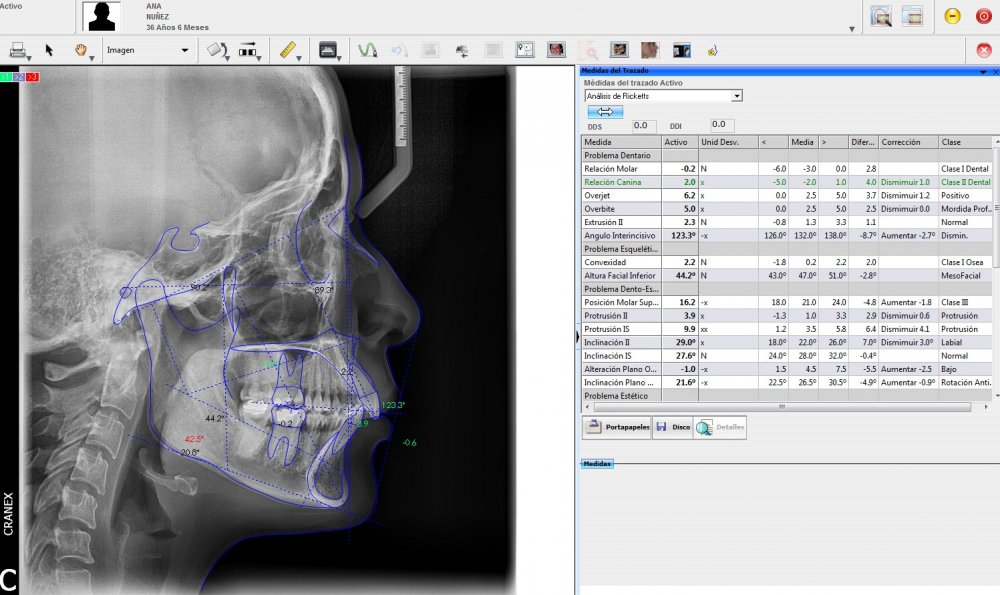

Inicio / Servicios / Análisis radiológico computarizado